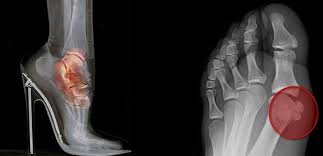

Fakat sadece doktorlar değil bazı modacılar bile bu akımı sağlıksız buluyor. İğne topuklar bilek burkulması, ayak tarağında çatlama ve eklem iltihabına neden olabiliyor. 7,5 cm’den uzun topuklar, düz tabanlı ayakkabılara oranla ayağa yedi kat daha fazla basınç yapıyor.

Çünkü bu yüksek topuklu ayakkabıların kadın bedenine vermiş olduğu zararlar bir hayli fazla gibi. Sadece doktorlar değil bazı modacılar bile yüksek topuklu ayakkabıyı sağlıksız buluyor. İğne topuklar bilek burkulması, ayak tarağında çatlama ve eklem iltihabına neden olabiliyor. 7,5 cm’den uzun topuklar, düz tabanlı ayakkabılara oranla ayağa yedi kat daha fazla basınç yapıyor.